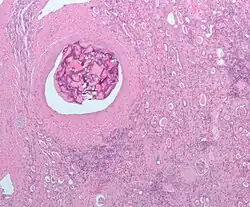

![]() Micrograph of embolic material in the artery of a kidney. The kidney was surgically removed because of cancer. H&E stain. |